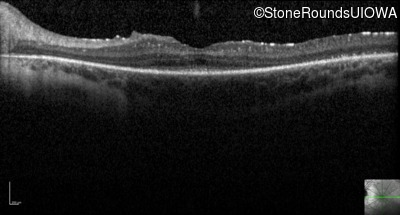

Optical Coherence Tomography - Right - 20/70

Exemplar / OCT Stack